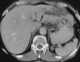

Papillary intraductal adenocarcinoma

Intraductal papillary mucinous neoplasm (IPMN) is a type of tumor that can occur within the cells of the pancreatic duct. IPMN tumors produce mucus, and this mucus can form pancreatic cysts. [Source: Wikipedia ]